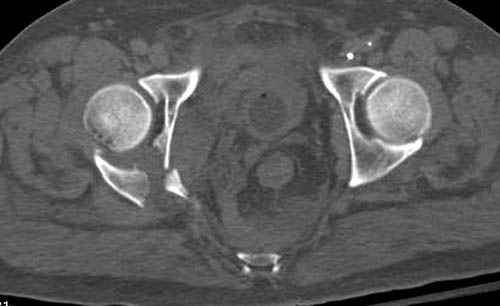

Дополнительно имеется перелом ацетабулума: задняя

колонна с полупоперечным переломом, и переломы костей лица.

На седьмой день зафиксирован перелом ацетабулума через задний доступ. Перед операцией для профилактики DVT, IVC фильтер, также получает Lovenox.

Снимки здесь....